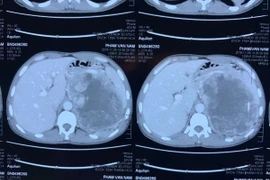

(khoahocdoisong.vn) - Nhờ sự chuyển giao kỹ thuật từ Bệnh viện Việt Đức và Bệnh viện Bình Dân, khoa Ngoại Tiết niệu - Bệnh viện Đa khoa tỉnh Thanh Hóa đã thực hiện rất nhiều kỹ thuật cao, kỹ thuật chuyên sâu chuyên ngành Tiết niệu và Nam học, cứu sống nhiều người bệnh. Một người bệnh có khối u tuyến thượng thận khổng lồ vừa được phẫu thuật thành công nhờ chuyên môn cao và thiết bị hiện đại.

U tuyến thượng thận (UTTT) là bệnh nguy hiểm không chỉ gây ảnh hưởng tới sức khoẻ, tinh thần mà còn khiến chất lượng cuộc sống giảm nghiêm trọng, dễ biến chứng tử vong. Nhờ sự chuyển giao kỹ thuật từ Bệnh viện Hữu nghị Việt Đức, Bệnh viện Đa khoa Thanh Hóa đã làm chủ kỹ thuật này, mổ cho bệnh nhân an toàn, nhanh hồi phục